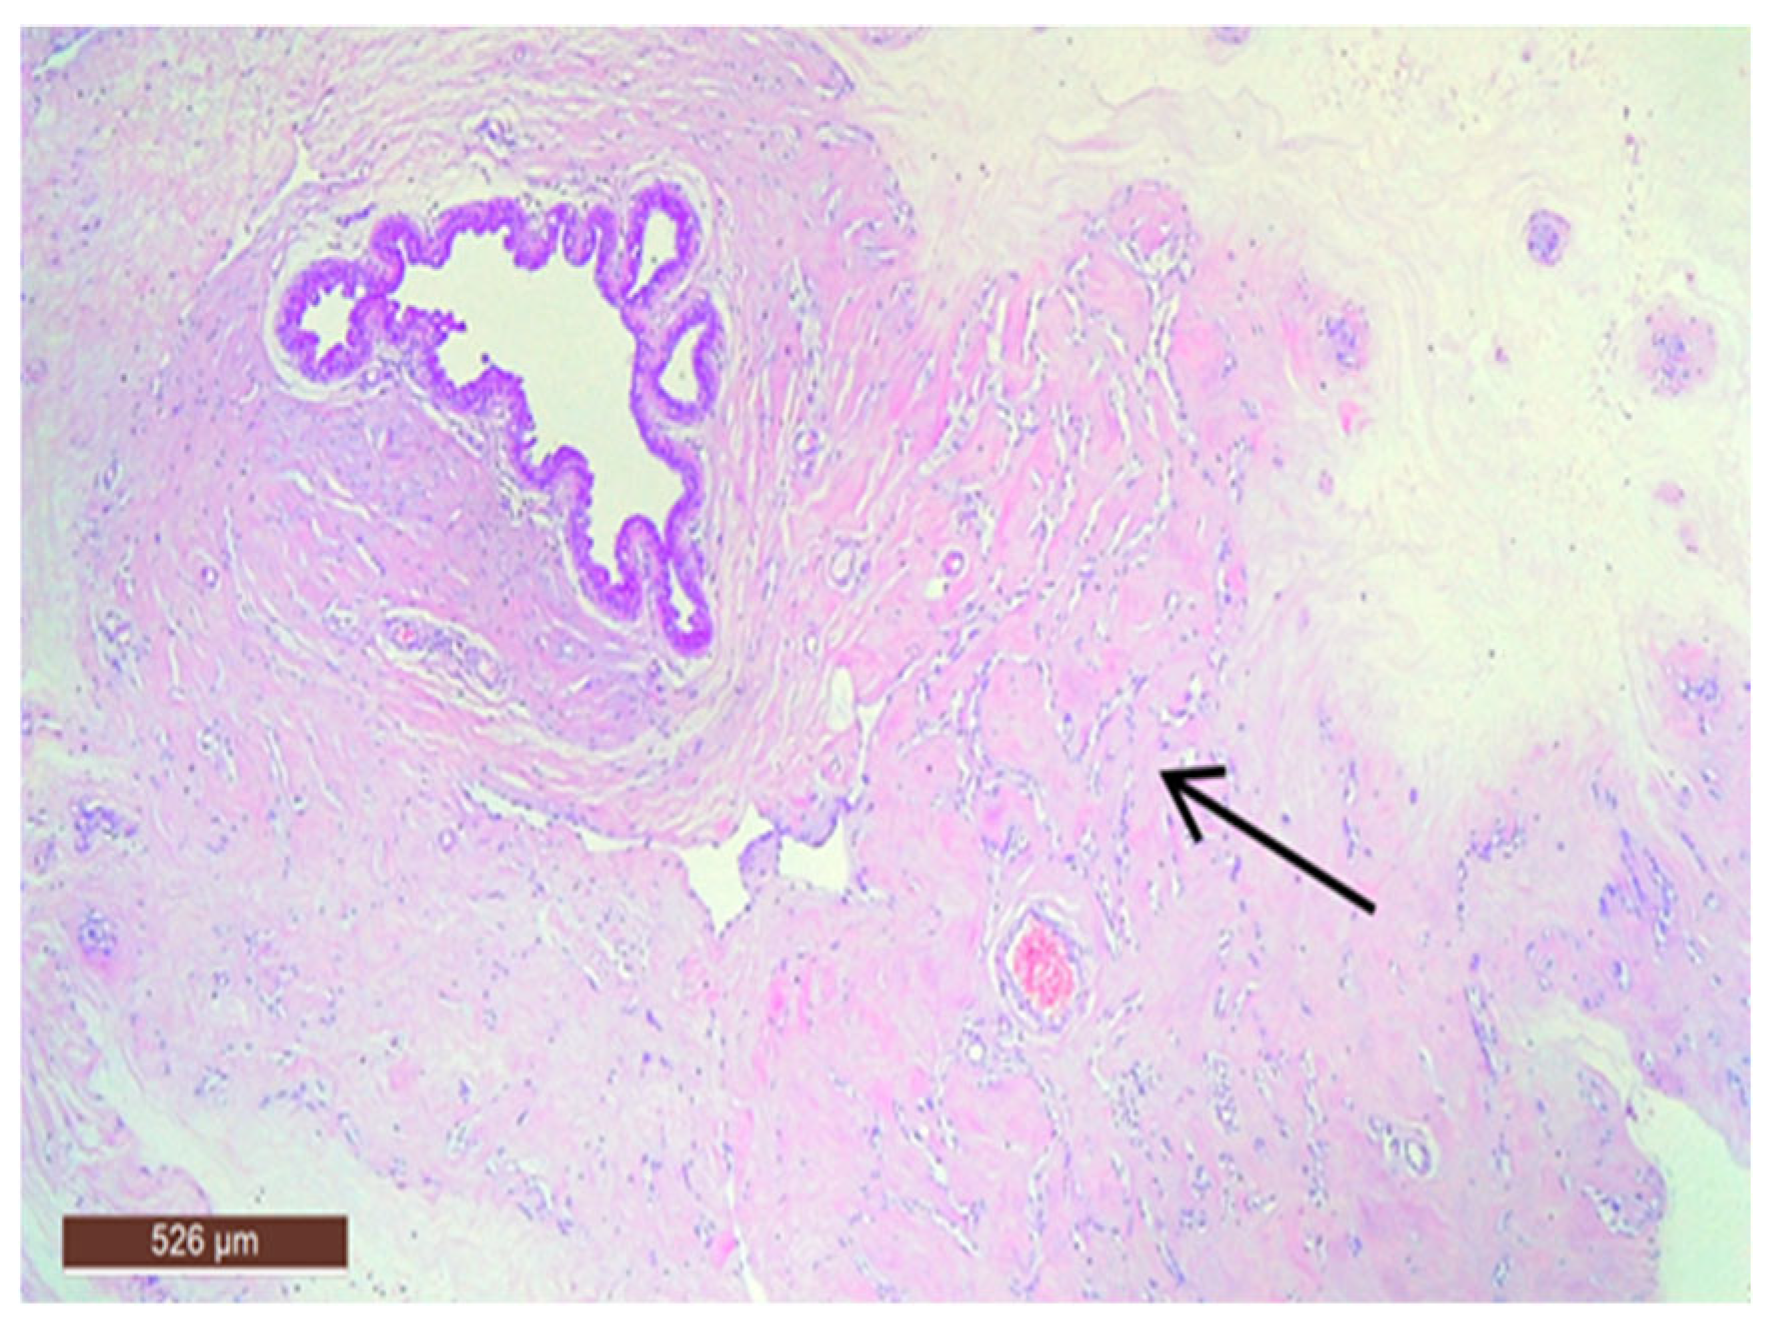

On microscopic examination, a hamartoma may exhibit three predominant components: glandular, fibrous and adipose (Figure 7). Epithelial components such as ducts and lobules are generally normal, featuring a single layer of epithelium overlying the myoepithelial cells. The fibrous component was composed of connective tissue stroma with a delicate connective tissue capsule (Figure 8). Additionally, the ducts within the hamartoma may display apocrine metaplasia (Figure 9).

The stromal component of the lesion is frequently hyalinized and poorly defined, extending around and infiltrating lobular structures, and may exhibit characteristics of pseudoangiomatous stromal hyperplasia (PASH) (Figure 10). Epithelial hyperplasia is uncommon, with only one case of atypical hyperplasia observed in our study.

Figure 8. Hamartoma with fine connective tissue capsule (arrow) (HE ×40).